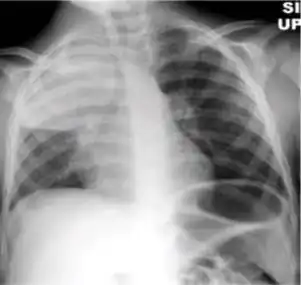

1. Infiltrate or consolidation - Opacification of airspaces within the lung parenchyma. Consolidation or infiltrate can be dense or patchy and might have irregular, ill-defined, or hazy borders.

Dense homogenous opacity in right, middle and lower lobe of primary pulmonary TB. -

Chest x-ray showing patchy opacification on the upper right and mid-zone lung with fibrotic shadows, as well as bilateral hilar lymphadenopathy. -